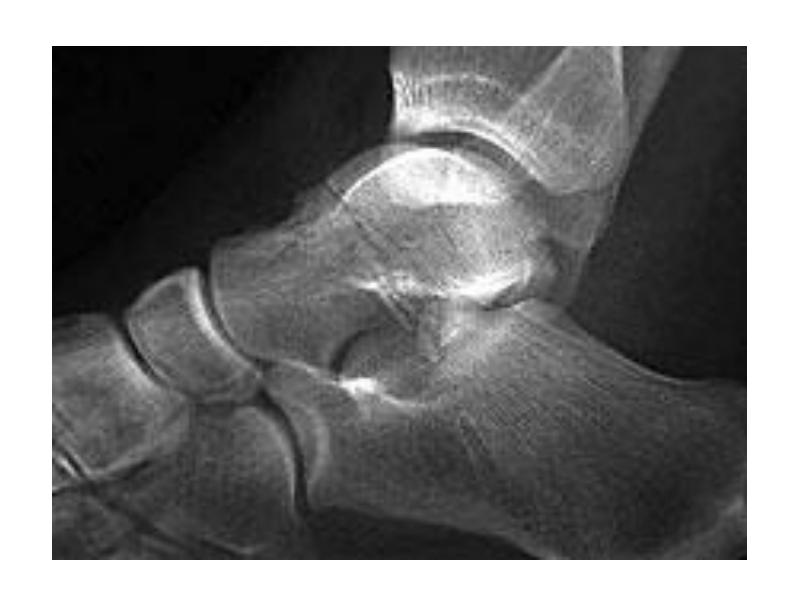

Talus Fractures

Fractured Talus

Complications: If displaced, can lead to avascular necrosis Treatment for displaced: ORIF or percutaneous fixation

Avascular Necrosis in Talus

Q1. What is the diagnosis?

- Fracture talus

Q2. Write complications specific to this fracture?

- Avascular necrosis